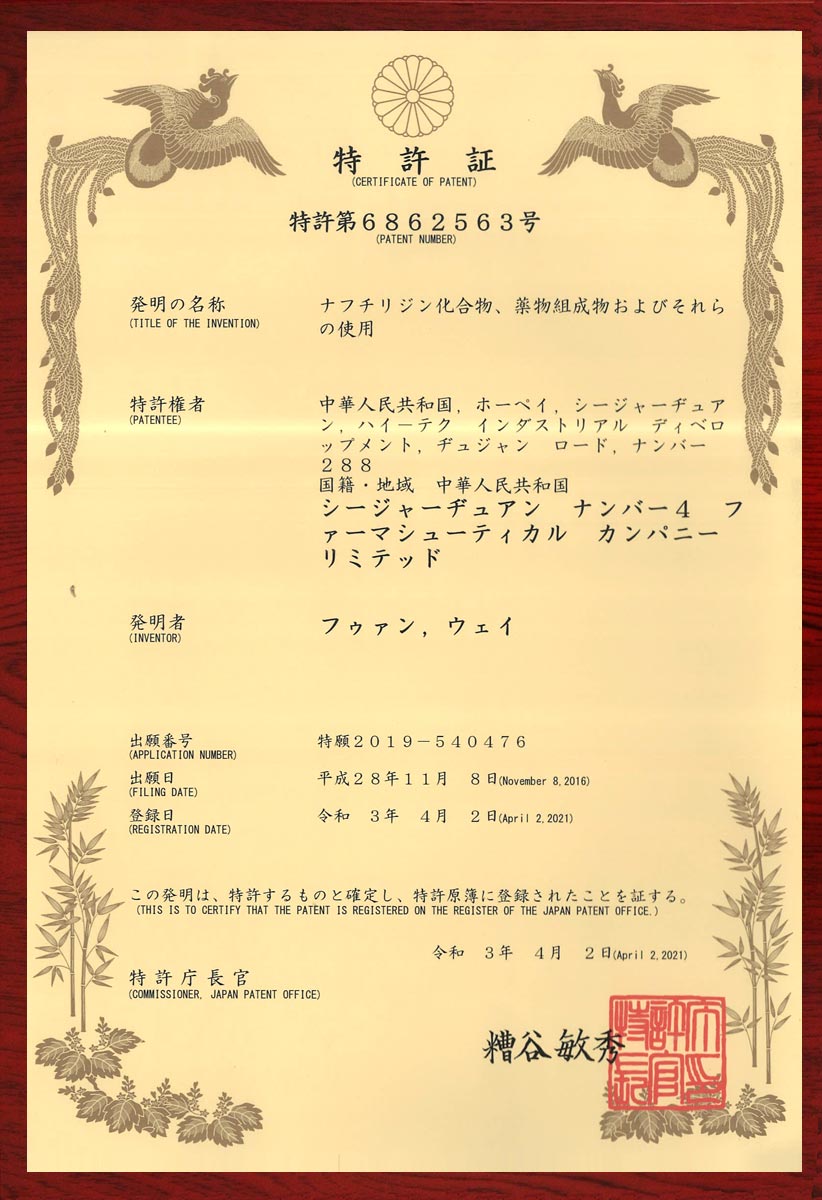

专利证书